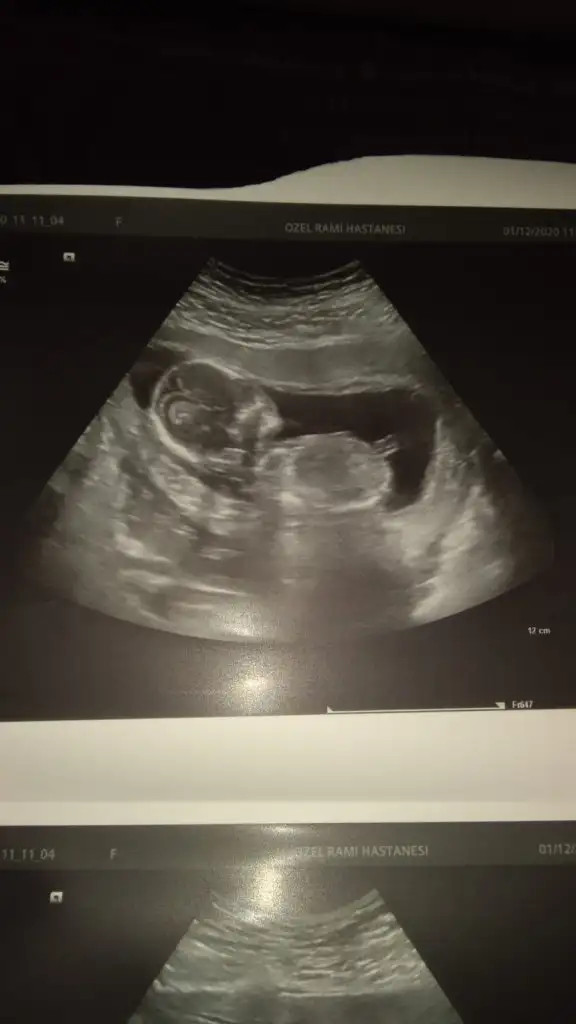

Başka USG varsa paylaşın emin olamadım sanki kız gibi 11 12 13 haftalar olmalı 14 değil renkle oynadım emin olmak için ama emin değilim tİkra meyra cnm bunuda bakarmısın 14haftalık

Daha küçük nub için 11 12 13 haftalar olmalıSevgili İkra Meyra,

Şimdilik erkek yönünde ama en iyi 11 12 13 haftalar olmalıRica etsem bize de bakar mısınızburada 10+4

çok teşekkür ederim❤Şimdilik erkek yönünde ama en iyi 11 12 13 haftalar olmalı